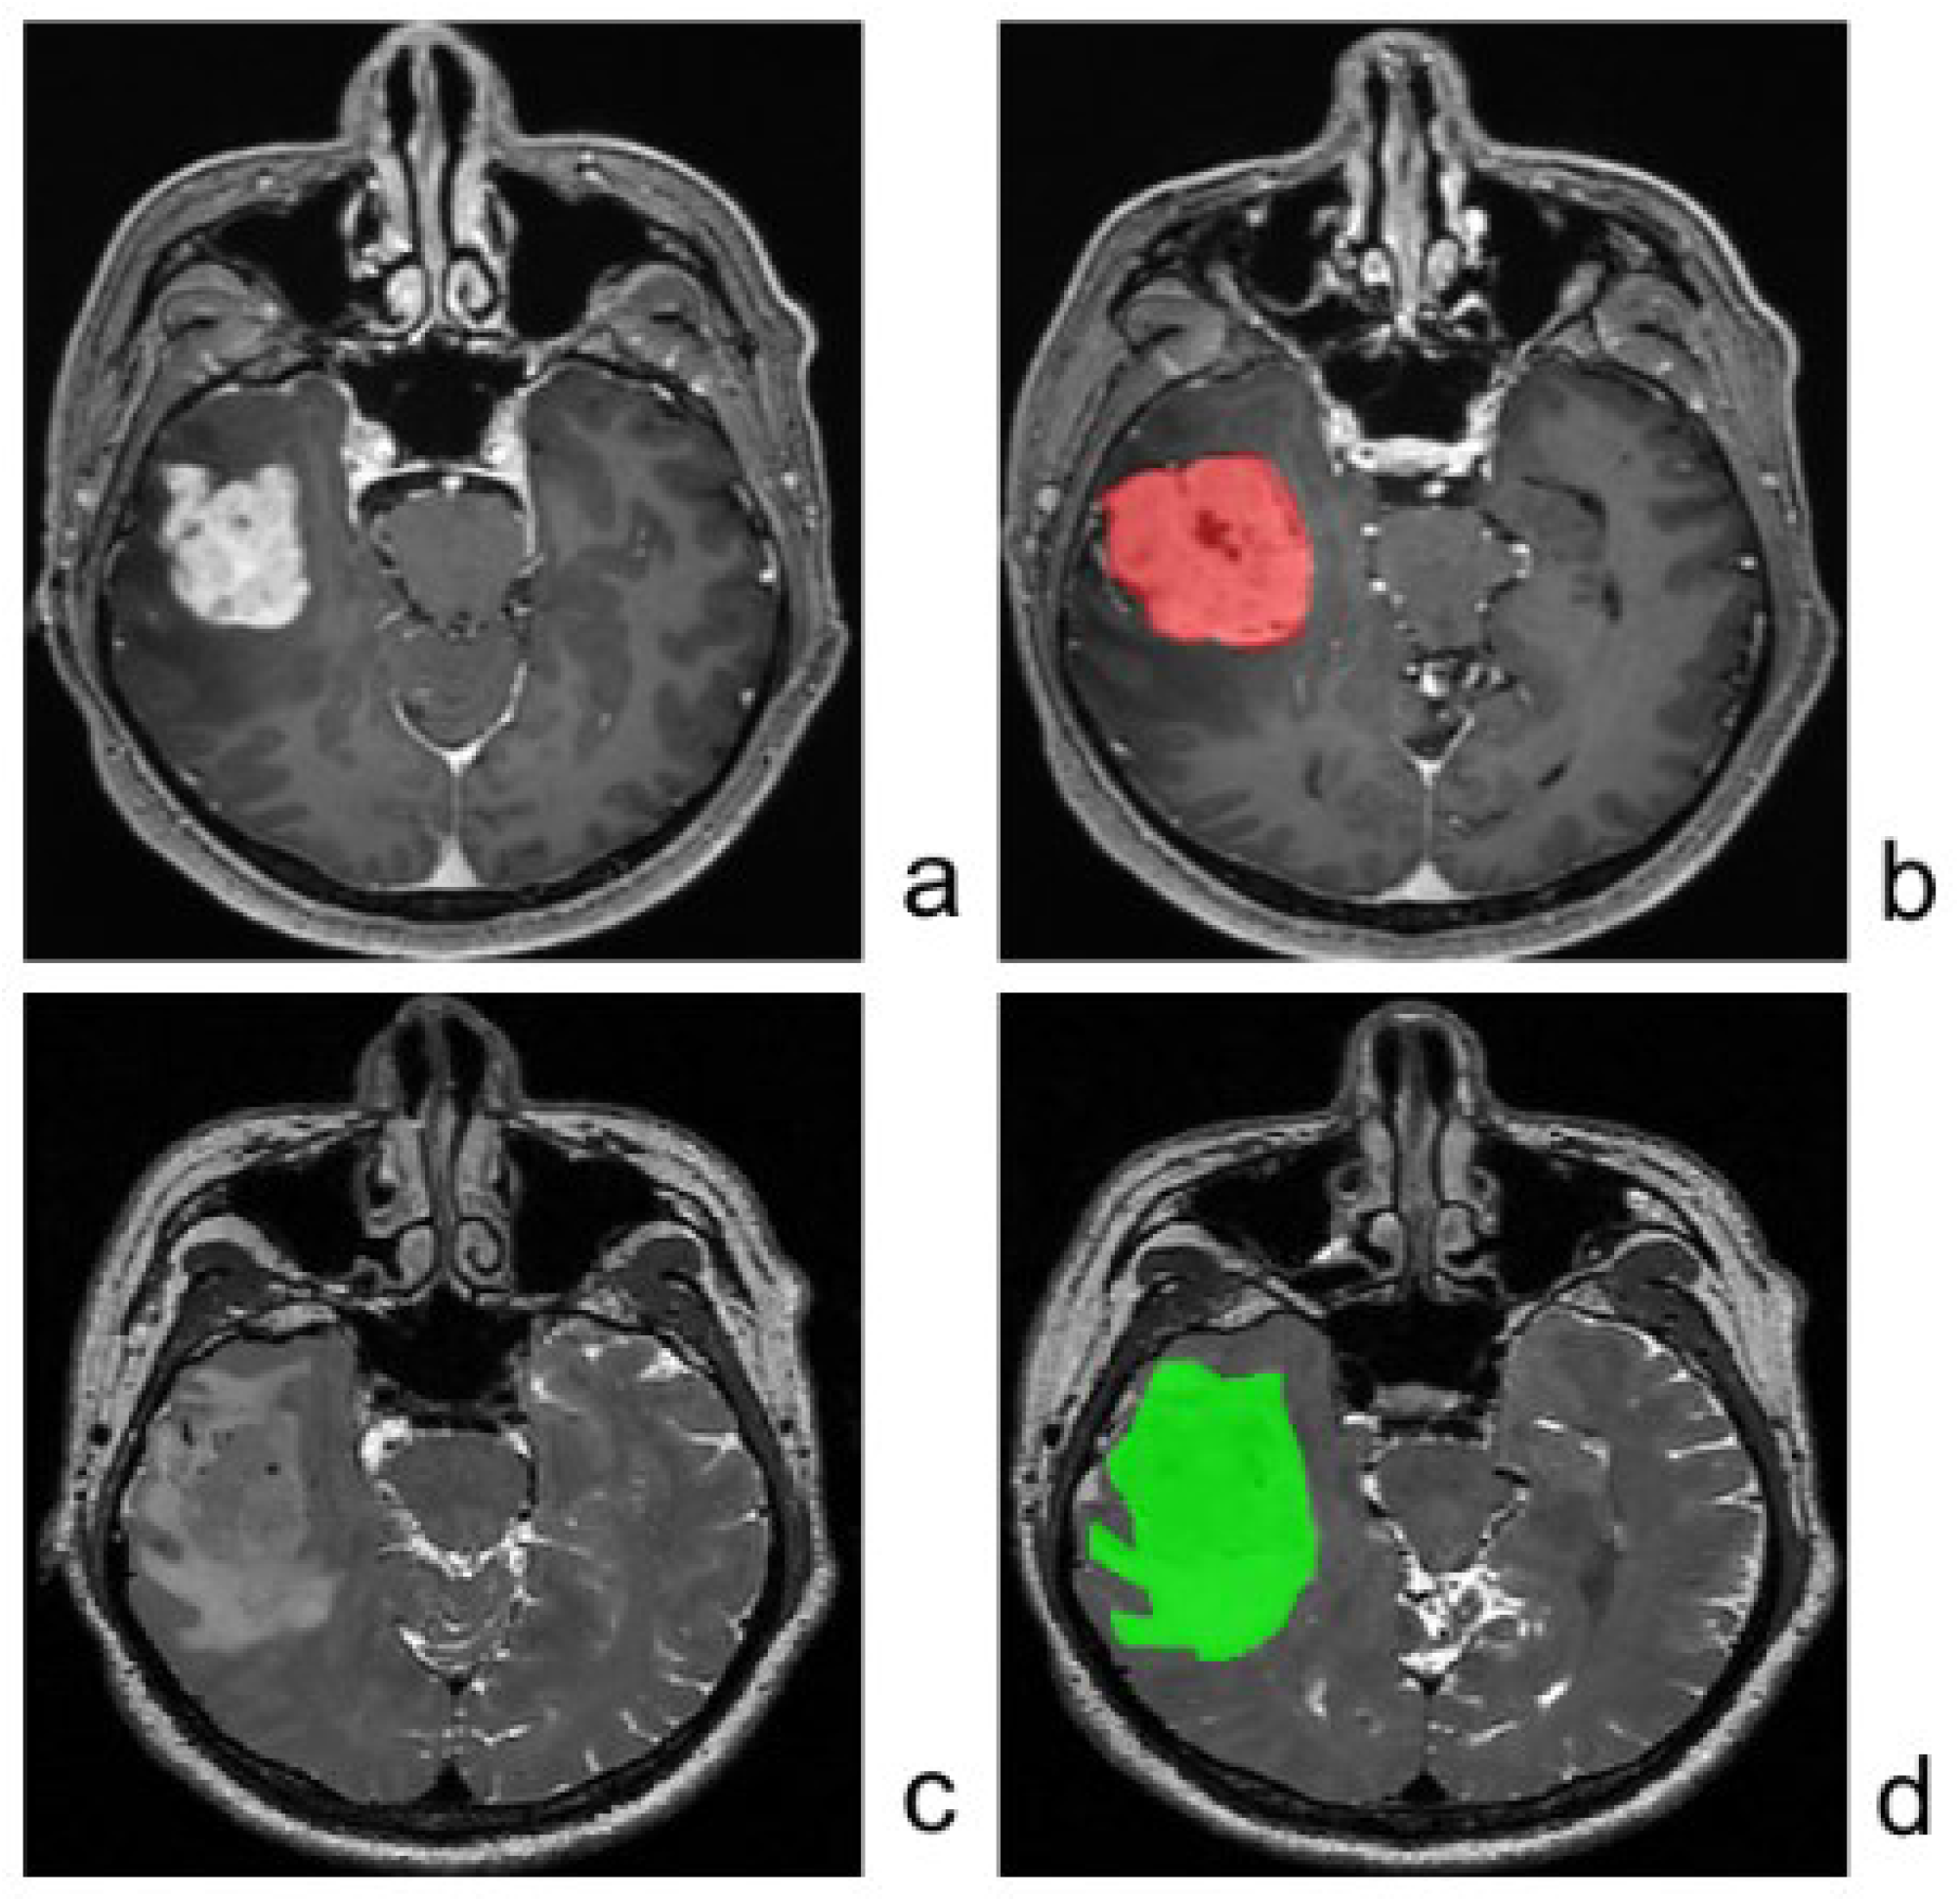

2.2. MRI Data and Image Preprocessing

2.3. Tumor Segmentation and Feature Extraction